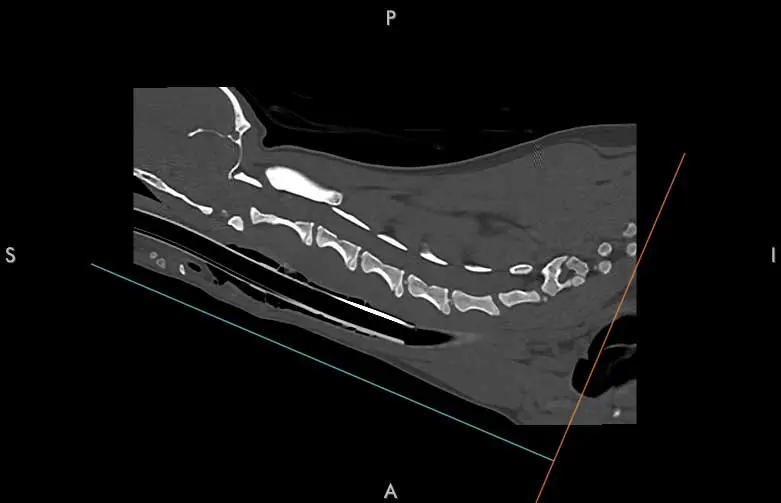

CT

This is most frequently used in emergency situations or if MRI is not available. Benefits include allowing the ability to create a quick 3D image reconstruction and providing good detail on bones, fractures and neoplasia, but it may not be able to pick up the finer detail of the inside of the spinal cord or nerves (Prager and Granger, 2024).